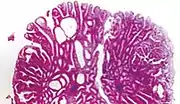

| Tubular adenoma | 2% at 1.5 cm[12] | Low to high grade dysplasia[13] | Over 75% of volume has tubular appearance.[14] | ![]() |

Micrograph of a tubular adenoma, the most common type of dysplastic polyp in the colon

Micrograph of a tubular adenoma – dysplastic epithelium (dark purple) on left of image; normal epithelium (blue) on right. H&E stain.